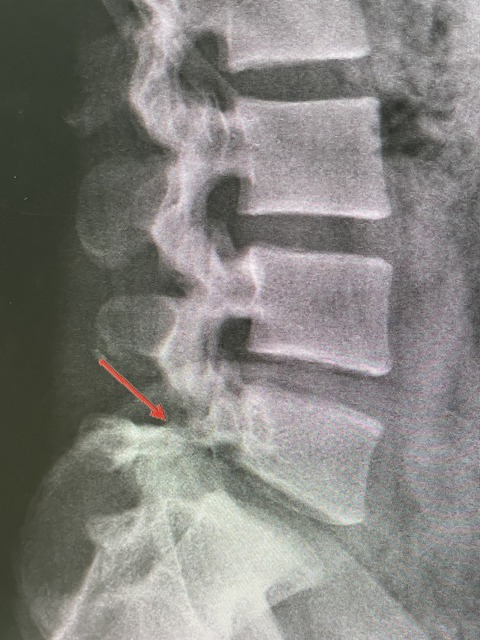

レントゲンを撮ると、強い分離症があり

現在は、分離症のサインあり、

分離症と診断し、トレーニングを開始しました